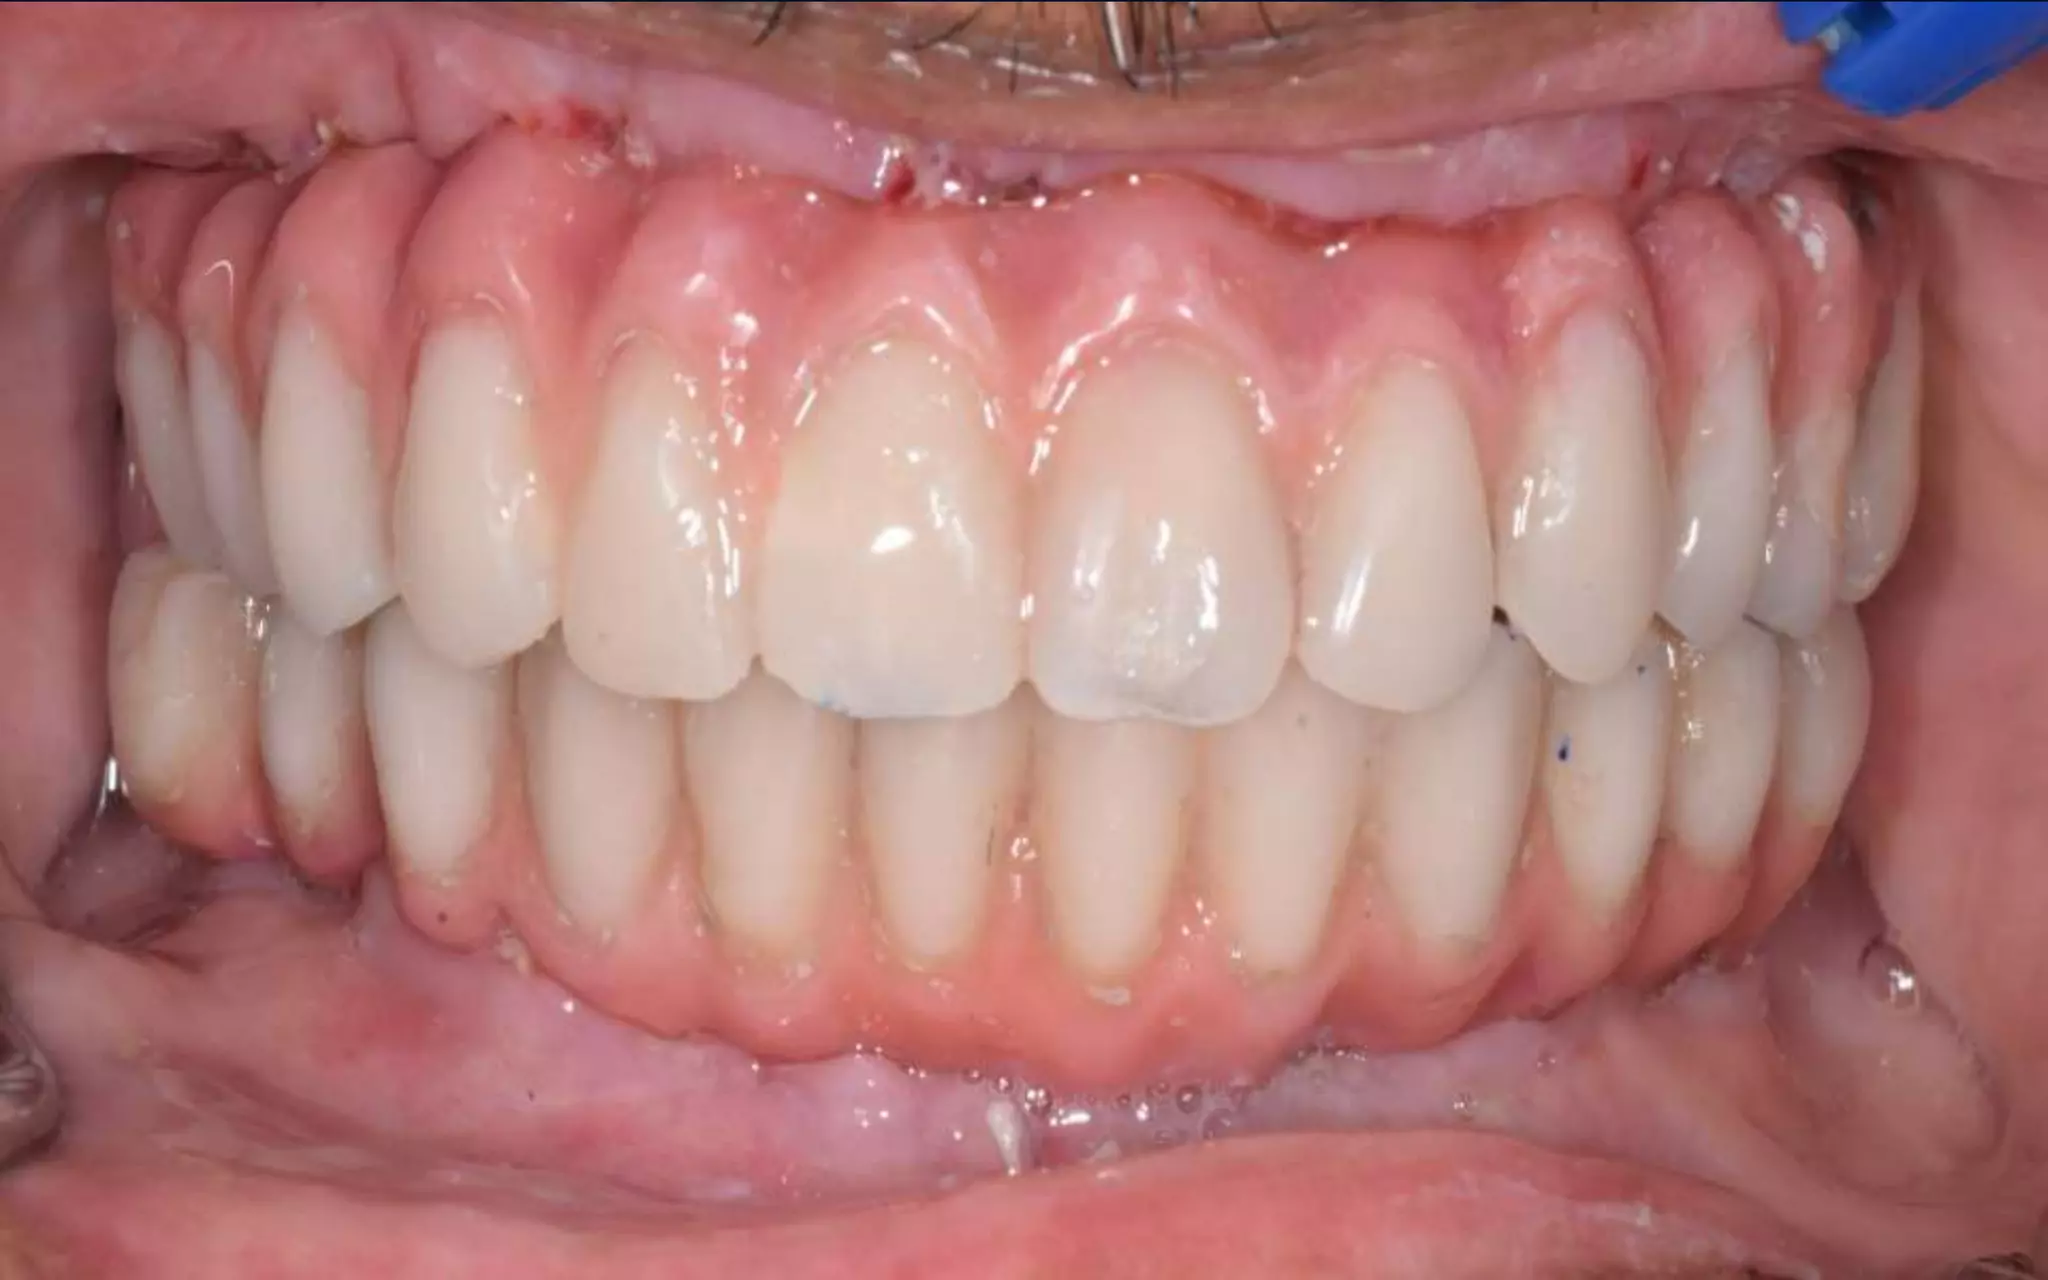

POST OPERATIVEVIEW

Porcelain FusedTo Metal

Bridge Cementation Done

Post operative view